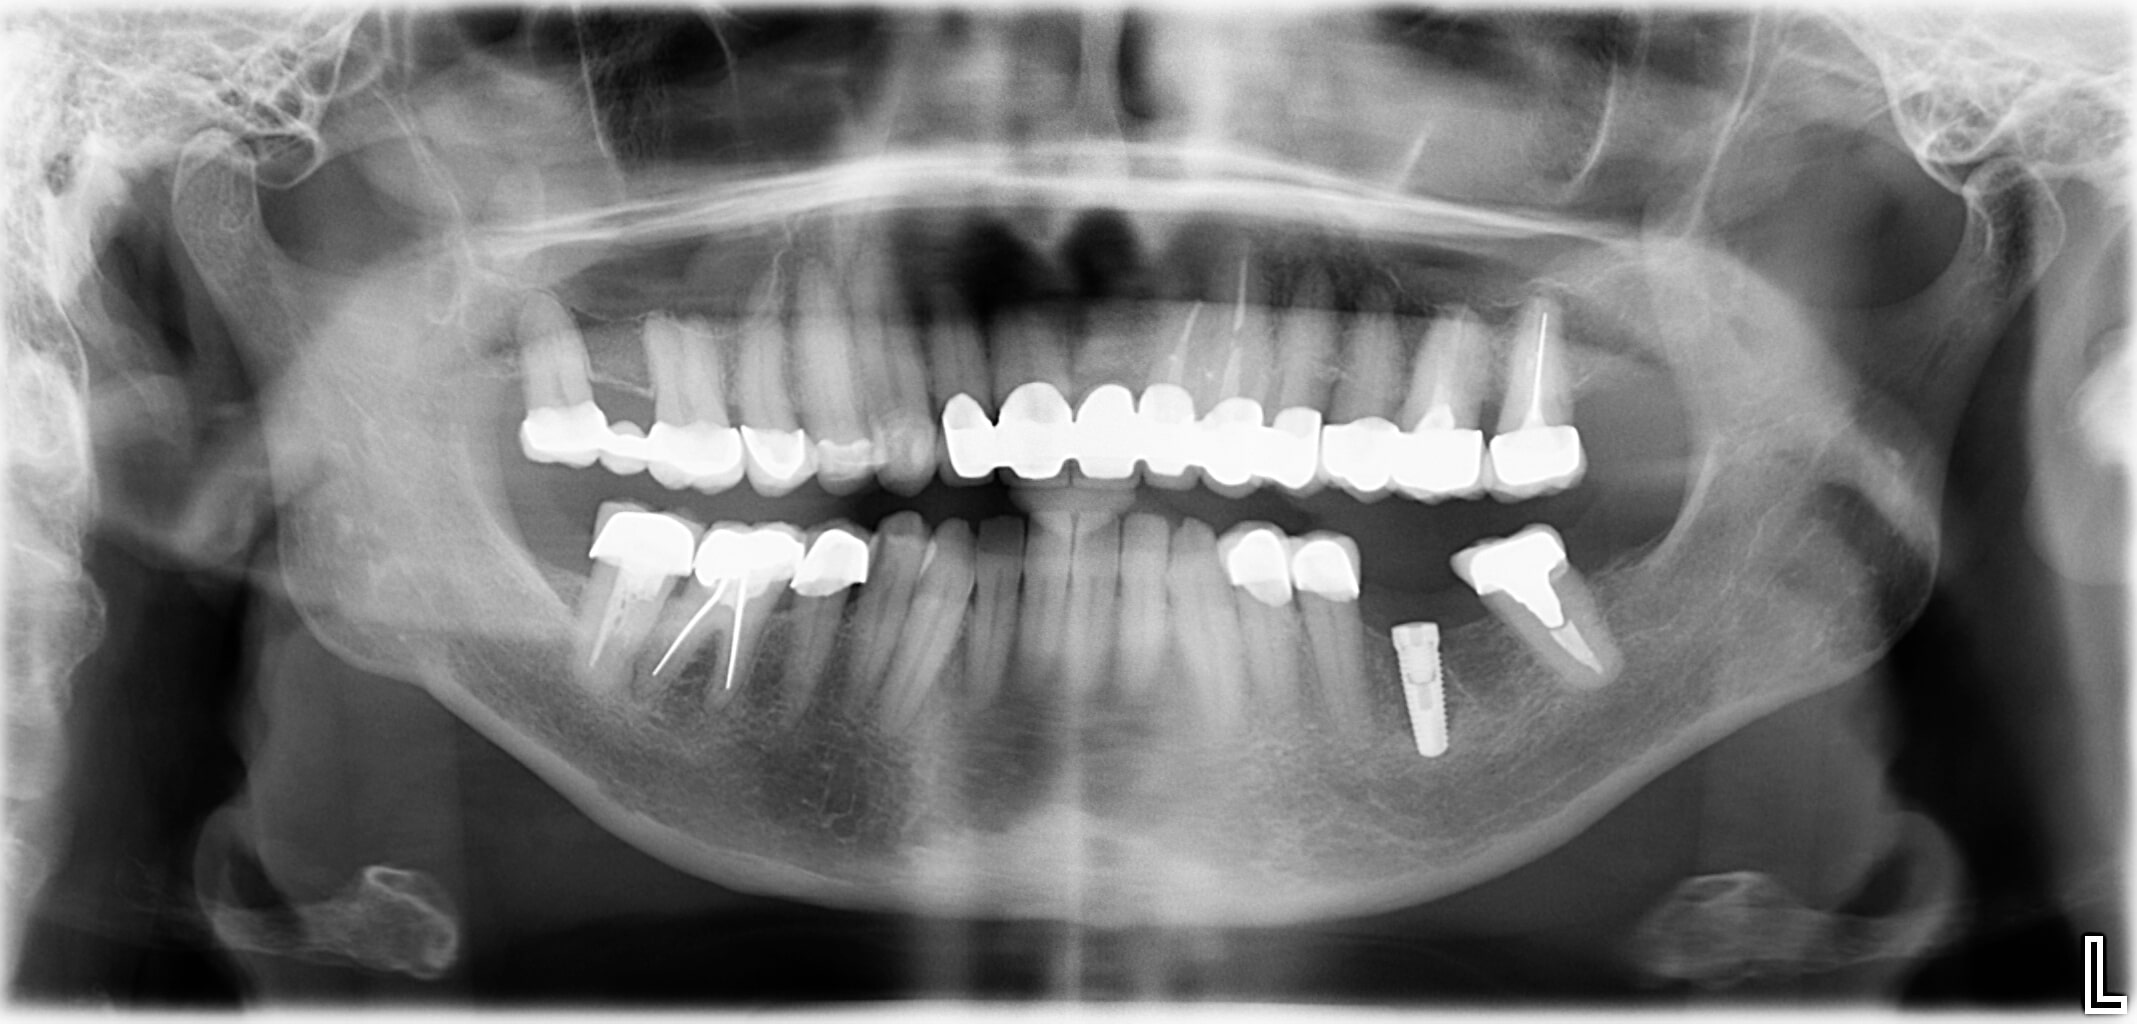

Wenn bei einer unvollständigen Zahnreihe nur ein oder zwei Zähne fehlen, sind meist Implantate die richtige Lösung.

Bei einer Implantation werden künstliche Zahnwurzeln eingepflanzt. Daran können Zahnkronen befestigt werden. Ein Beschleifen der Nachbarzähne (wie es bei herkömmlichen Brücken oft nötig ist) ist dabei nicht notwendig.

- Implantatgetragener Zahnersatz anstelle einer Brücke oder herausnehmbarer Teilprothese

- Fehlende Zähne werden Zahn-für-Zahn mit Implantaten ersetzt